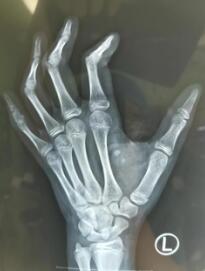

术前X线检查